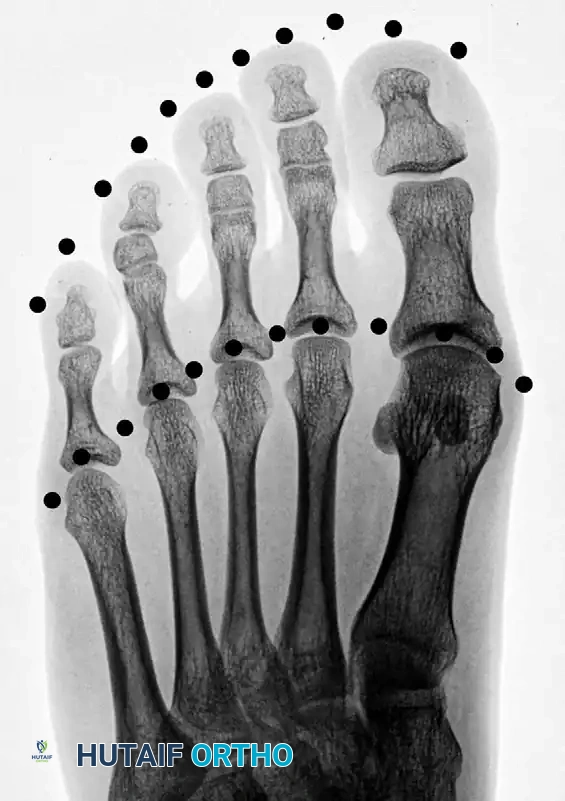

Radiographic evaluation requires standard weight-bearing anteroposterior (AP), lateral, and oblique views of the foot. On the AP radiograph, the normal metatarsal parabola can be traced to identify the exact degree of shortening.

Figure 1: Normal toe-tip and metatarsal head parabolas (dotted lines), demonstrating the ideal geometric arc required for optimal forefoot biomechanics.